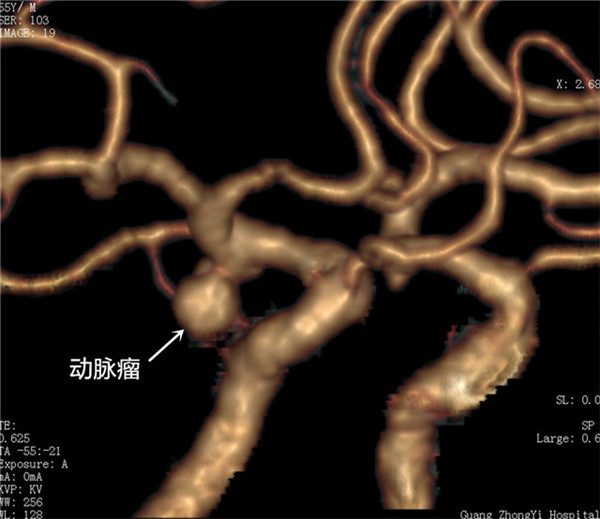

患者陆某某,男,58岁,因“右侧眼睑下垂、视力障碍半月”入院。诊断:1.右侧后交通动脉瘤,2.右侧动眼神经麻痹。入院后予以开颅动脉瘤夹闭手术并切除动脉瘤。术后2周,患者眼睑逐渐能睁开,眼球恢复活动,视力恢复。

术前CTA右侧后交通动脉瘤